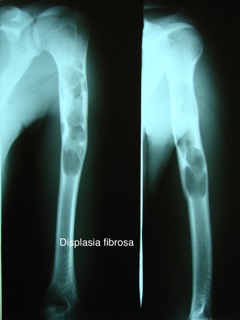

Displasia fibrosa

É uma doença, congênita e benigna,1 que provoca desgaste ósseo e crescimentos ou lesões em um ou mais ossos do corpo humano. Estas lesões são crescimentos semelhantes a tumores que consistem na substituição do osso medular pelo tecido fibroso, causando a expansão das áreas e enfraquecimento dos ossos envolvidos. Especialmente quando envolvendo ossos do crânio ou face, as lesões podem causar deformidades visíveis externamente. O crânio é, frequentemente, mas não necessariamente, afetado.